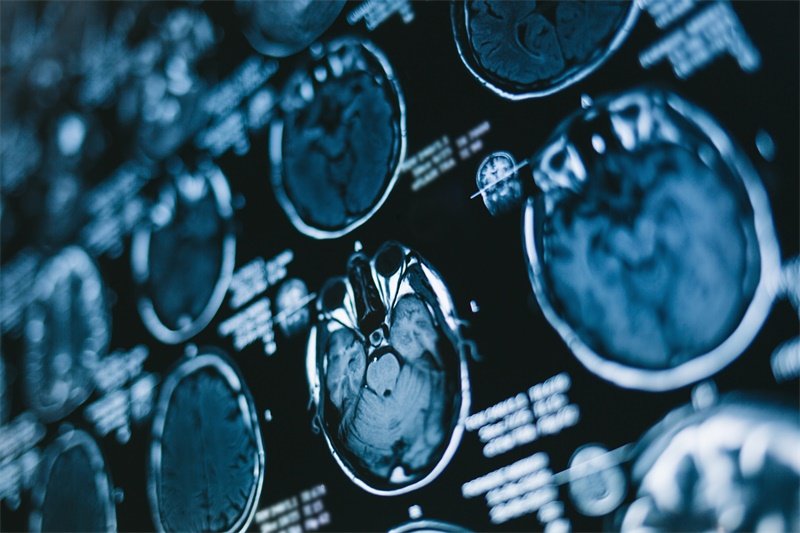

影像学检查是诊断右侧小脑角环池区占位的重要手段。最常见的检查方法包括MRI(磁共振成像)和CT(计算机断层扫描)。

MRI检查通常能够提供更清晰的软组织图像,对于小脑及其周围结构的评估特别有效。通过这些影像学资料,医生能更好地判断占位的性质、大小和位置。

在CT扫描中,医生能观察到脑脊液空间的变化,如环池区的扩大或压迫现象。这些影像学特征对临床诊断和后续治疗决策都具有重要意义。